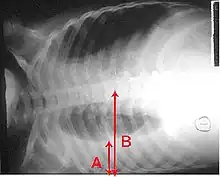

The World Health Organization has defined pneumonia in children clinically based on either a cough or difficulty breathing and a rapid respiratory rate, chest indrawing, or a decreased level of consciousness.[65] A rapid respiratory rate is defined as greater than 60 breaths per minute in children under 2 months old, greater than 50 breaths per minute in children 2 months to 1 year old, or greater than 40 breaths per minute in children 1 to 5 years old.[65]

In children, low oxygen levels and lower chest indrawing are more sensitive than hearing chest crackles with a stethoscope or increased respiratory rate.[66] Grunting and nasal flaring may be other useful signs in children less than five years old.[67]